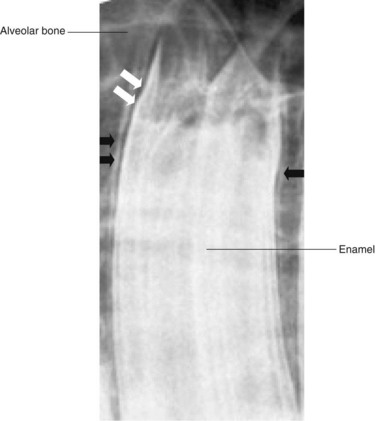

Enamel, dentin, and cementum (along with bone) are the densest materials in the body, and therefore the cheek teeth appear as very radio-opaque structures, within which the radiolucent pulp horns may be seen running longitudinally. Dentin and cementum have a lower proportion of mineral content than enamel and have a radio-opacity similar to bone.2 Younger cheek teeth contain little dentin relative to aged cheek teeth, and are, therefore, comparatively radiolucent.2 The reserve crown of the cheek teeth is attached to the alveolar bone by the periodontal ligament, which is evident radiographically as a narrow parallel radiolucent line between the tooth and the alveolus (Fig. 13.28). This space lies adjacent to a radiodense rim of cortical alveolar bone, radiographically, termed the lamina dura, which lines the alveolus (Fig. 13-28). Although disruption of this structure can occur with dental disease, the irregular contour of equine cheek teeth means that the lamina dura may not be visible on some radiographic projections of normal teeth, and (in contrast to brachydont radiographs) absence or partial discontinuity of the lamina dura is not a reliable indicator of apical or periodontal disease.9,10 The area of the periodontal ligament may widen due to disease processes, but the apices of young equine cheek teeth also have wider radiolucent areas adjacent to the lamina dura in the area of the eruption cysts (Fig. 13.29).

image

Fig. 13.28 Close up X-ray of a maxillary cheek tooth. The lamina dura (black arrows) is a linear radio-opacity that lines the alveolus. Note that the lamina dura denta is not visible along the entire contour of this normal tooth. The periodontal ligament (white arrows) is represented by a radiolucent area between the lamina dura and the periphery of the tooth.